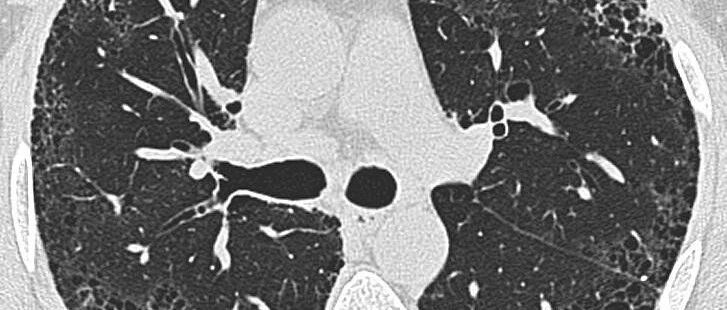

特发性肺纤维化影像识别,一文搞定!│以影识病

来源:医脉通呼吸频道

时间:2020-10-25